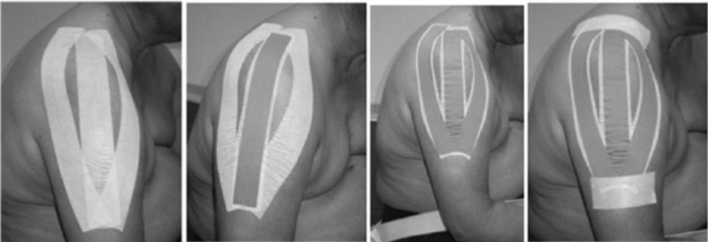

Đai đỡ vai (sling) và Băng dán (tapping)

Bán trật khớp vai có thể là yếu tố góp phần gây đau vai ở bệnh nhân đột quỵ. Một số biện pháp nâng đỡ bên ngoài đã được đề xuất nhằm điều chỉnh bán trật khớp vai. Hiệu quả các biện pháp đeo nẹp hoặc băng dán như vậy vẫn còn bàn cãi.

Khi trương lực cơ và cơ lực quanh khớp vai đã cải thiện đủ để phòng ngừa bán trật khớp vai, có thể ngừng các dụng cụ hoặc biện pháp nâng đỡ bên ngoài. Cần kết hợp một chương trình tập luyện phù hợp với bệnh nhân đeo đai.

Tuy nhiên, một số tác giả cho rằng đai đỡ vai có thể giữ chi thể ở một tư thế xấu (như gập khuỷu tay), có thể gây co rút mô mềm và ảnh hưởng bất lợi lên sự đối xứng, thăng bằng (dễ ngã), và hình ảnh cơ thể.